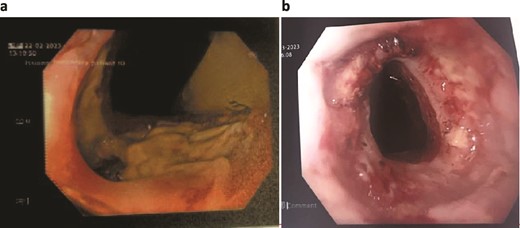

Unfortunately, the patient developed respiratory sepsis and a small bowel obstruction, requiring ICU readmission and intubation. An exploratory laparotomy on postoperative day 5 showed no evidence of ischemia or perforation. A subsequent OGD on postoperative day 8 revealed a 20% staple line defect (Fig. 4a), leading to VACStent and right chest drain insertion.

Patient Four: (a) Before VACStent insertion, showing the oesophageal defect. (b) After VACStent treatment, demonstrating successful defect closure.

Following the removal of the VACStent on postoperative day 13 (Fig. 4b), the patient underwent a prolonged antibiotic course and received dietician support for jejunal feedings. Despite complications, including unsuccessful extubation and bilateral pleural effusions, the patient gradually improved with comprehensive care. A drain was placed on postoperative day 23 to address chest wall collections, and the patient was weaned off the tracheostomy by day 31. The patient continued to recover, managed hypertension, and was discharged home on day 82, with various supports in place and a follow-up scheduled in the clinic.